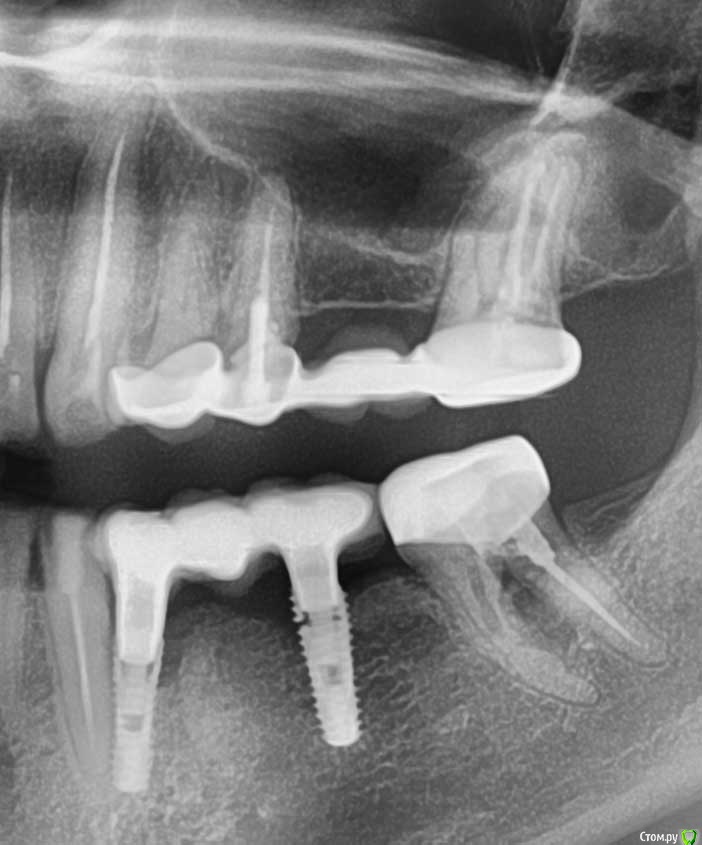

В апреле 2020 года была проведена имплантация на месте 34 и 36 зубов (корейская система INNO implant submerged 3.5x12, 4.0х12).

В июле 2020 года на импланты был установлен металлокерамический мост на приливаемых абатментах (винтовая фиксация). По состоянию на 20.11.2020 (4 месяца под нагрузкой) жалоб не было.

22.01.2020 ослабли винты на имплантах, был сделан новый снимок, где обнаружилось, что имплант на месте 36 сломался.

Снимки прилагаю.

post-62133-0-04030700-1611750728_thumb.jpg